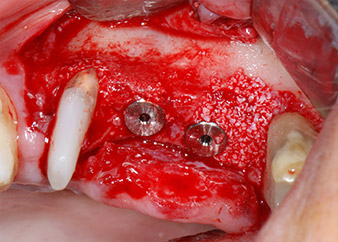

Implant beds were prepared at sites 25 and 26 with rotary instruments, used in a contra-angle handpiece with a 20 : 1 transmission ratio with an updated powerful implant motor (Implantmed, W&H) (Fig. 8).

The final preparation next to the sinus was again carried out with a piezoelectric instrument (Piezomed, insert S2).

Prior to implant placement, and following verification of an intact Schneiderian membrane (Fig. 9), the internal sinus floor was augmented at both implant sites by means of xenogeneic bone substitute material (Bio-Oss, Geistlich Biomaterials) (Fig. 10).

The implants (Restore, Keystone Dental, diameter 3,75 mm, length 8.0 mm) were placed with the implant motor

(Figs. 11 and 12).